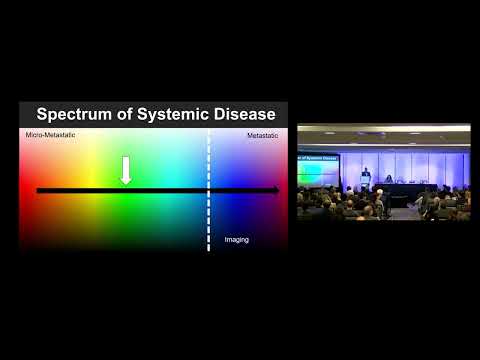

DEB03: Resection of Oligo Metastatic Liver Disease in Pancreatic Cancer Patients: Yes/No

Debate 03:Resection of Oligo Metastatic Liver Disease in Pancreatic Cancer Patients: Yes/No